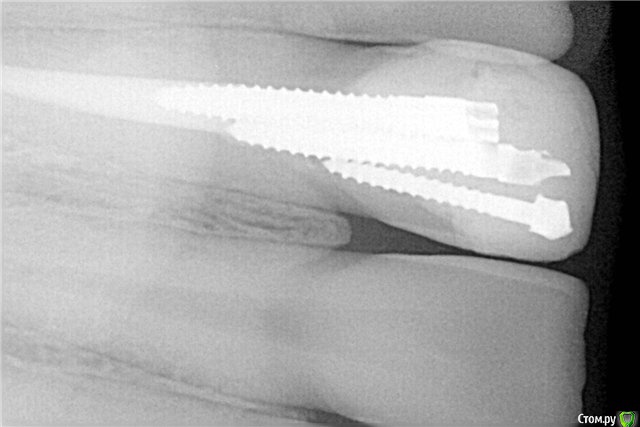

арис Опубликовано 3 сентября, 2015 Поделиться Опубликовано 3 сентября, 2015 Про простоту - тут наверное кто к чему приловчился.Я как-то видела продольные распилы с термафилом где по снимку всё красиво вроде-бы, в по факту один стержень к стенке торчит без гутты. как-то не порадовало..так говорят же,что не важно чем обтурировать канал,главное чтобы там не было пустоты. Так какая разница носитель там или гутта? А так правильно вносить надо и не будет носительоголяться. Ссылка на комментарий

inSight Опубликовано 5 сентября, 2015 Поделиться Опубликовано 5 сентября, 2015 (изменено) Я как-то видела продольные распилы с термафилом где по снимку всё красиво вроде-бы, в по факту один стержень к стенке торчит без гутты. как-то не порадовало..+100! Для подтверждения ваших слов. Фото с ФБ Дмитрий Куликов (надеюсь не обидеться) Сорь не знаю как уменьшить картинки http://s017.radikal.ru/i419/1509/a3/04df66f38283t.jpghttp://s019.radikal.ru/i636/1509/15/8def9c187a9ct.jpg http://s019.radikal.ru/i623/1509/dd/1b50fe45eb29t.jpg Изменено 5 сентября, 2015 пользователем inSight 1 Ссылка на комментарий